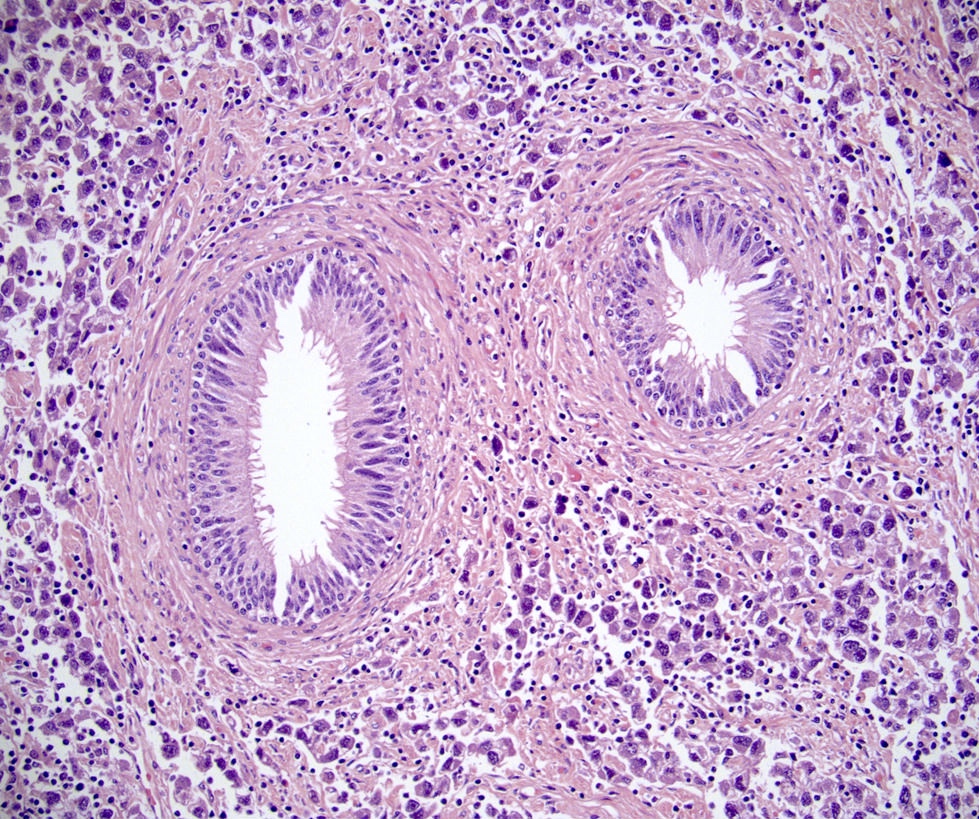

Microscopic (histologic) images

- LVI

- Freshly cut or minimally fixed testicular germ cell tumors have frequent tissue displacement artifact ("butter"), which confounds the diagnosis of true LVI (classified as pT2) (Am J Clin Pathol 2016;145:341)

- Care must be taken when grossing to decrease the amount of tissue displacement artifact and overnight fixation of a bivalved specimen may be helpful

- Histologic features supporting true LVI are tumor emboli that are cohesive, have smooth contours and adhere to the vessel wall (Am J Clin Pathol 2016;145:341)

- LVI of the spermatic cord is pT2 not pT3